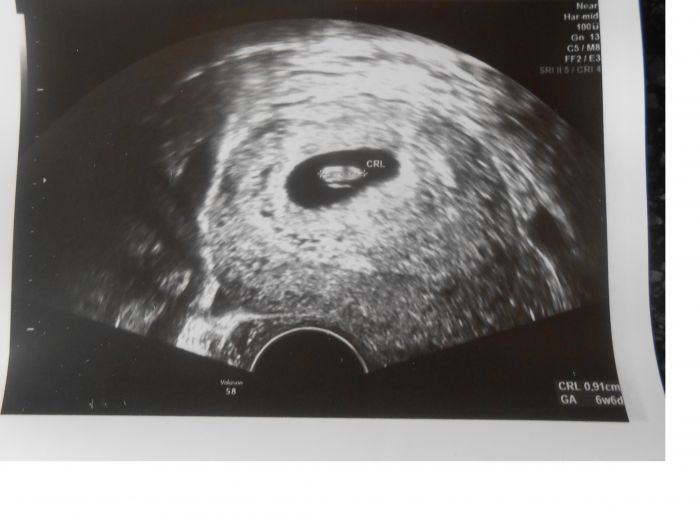

Neni no :) ale co uz :) je to jeste prcek, nikdy jsem se v te fotce nevyznala, kdyz mi ji někdo cizi ukazoval, ale kdyz je moje vlastní tak ho hned poznám :)))